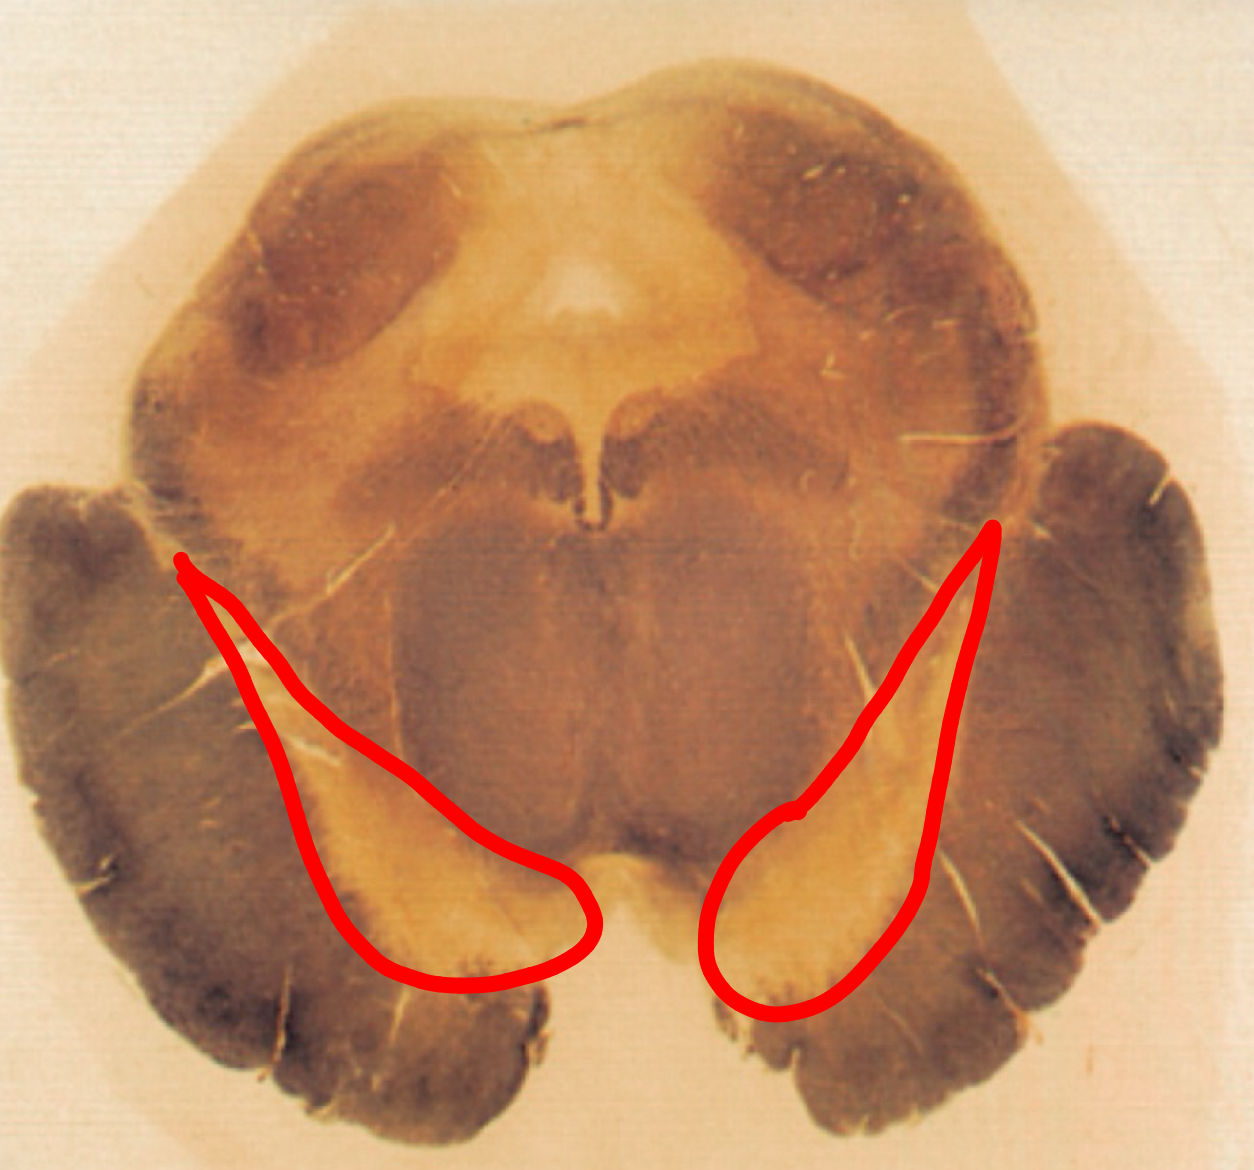

fastigial nucleus

interposed nucleus (globose + emboliform)

dentate nucleus

posterior lobe

vermis

tonsils

flocculus

nodule

cerebellar peduncles

4th ventricle